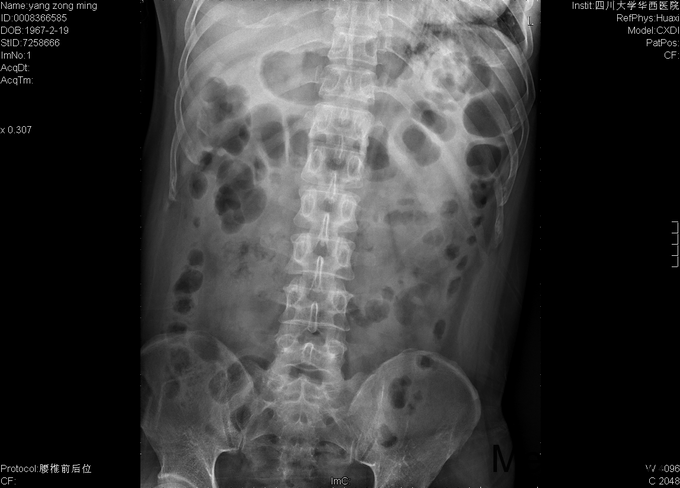

男,48岁8月,因“腰部疼痛伴右腿疼痛1+月”入院。患者1+月前出现腰部疼痛,伴右侧臀部、大腿后部、足背疼痛,大腿后部为主,不影响行走,不伴行走不稳、下肢麻木等,于外院行理疗、针灸等保守治疗,症状未见明显缓解。后症状有所加重,变换体位时疼痛加重,开始出现夜间痛醒,行走困难,遂至当地医院行靶点射频、封闭等治疗(具体不详),效果不佳,于2015-9-28入我院疼痛科,给予对症治疗(具体不详),症状有所缓解,现为进一步治疗入我科。

专科情况:视:双下肢等长,皮肤黏膜完整,无破损,双下肢肌肉无萎缩,脊柱外形正常。触:腰5-骶1棘突间压痛,腰部VAS疼痛评分5分,右下肢VAS疼痛评分6分,右下肢针刺觉减退。动量:四肢肌力、肌张力正常。右侧直腿抬高试验(+),加强实验(+),加强实验(-),双侧髌骨研磨试验(-)。生理反射均正常引出,病理征阴性。辅助检查:2015-9-29数字化X光腰骶椎正侧位摄影示:腰骶退行性病变、骨质疏松。数字化X光胸部正侧位摄影示:心肺未见明显异常。CT椎体一个部位骨三维成像扫描示:1、腰椎退行性病变,L5/S1椎间盘稍向右后突出2、骶管囊肿。MRI腰椎普通扫描示:1、L5/S1椎间盘突出2、腰椎退行性病变。

初步诊断:1、腰5骶1椎间盘突出症;2、骶管囊肿;3、骨质疏松。经皮内镜右侧椎间孔入路腰5骶1椎管减压+椎间盘髓核摘除+射频成形术